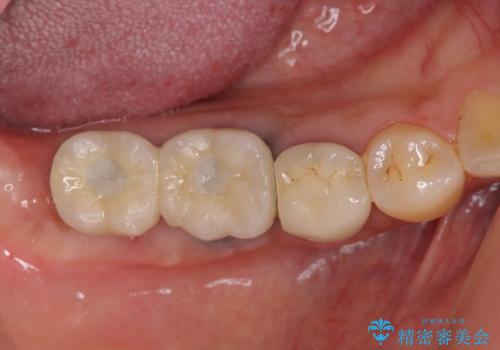

臼歯部インプラント治療

- 失った右下奥歯の機能回復を求めて来院されました。

取り外しの必要な入れ歯、もしくは手術の必要なインプラントのご提案を行い、しっかりと奥歯で物を噛みたいとの要望からインプラント治療を計画します。